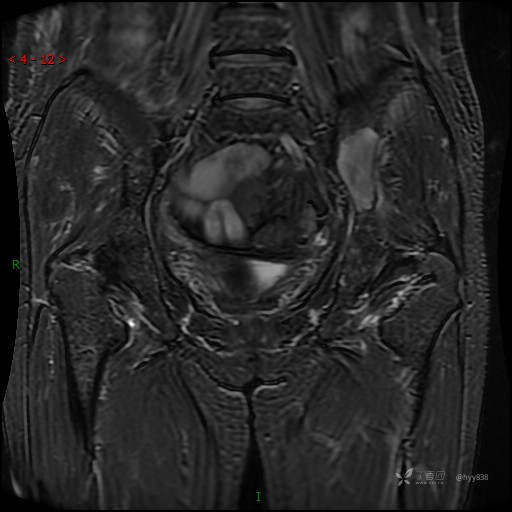

MRI T1WI+T2WI axi

Cor T1WI T2WI -fs